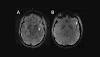

7T MRI scans provide a high-res look at how migraines affect the brain (A) Cerebral microbleeds (CMB) visualized as round, dark lesions (arrow) on SWI sequence in the left temporal lobe in a migraine case with aura. (B) Asymmetry in the appearance of the cortical vessels is more prominent on the left side (arrow) ...